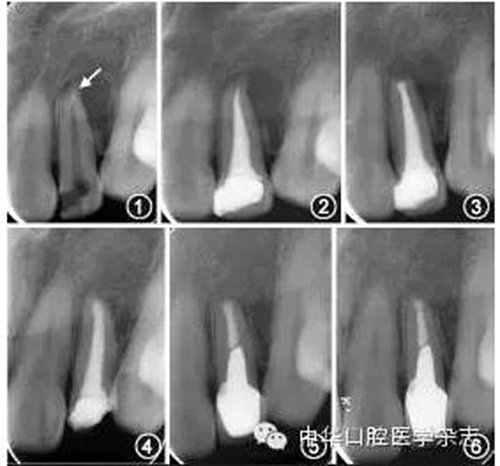

常用的非手術(shù)治療方法包括采用顯微超聲技術(shù)從根管內(nèi)取出分離器械、在分離器械側(cè)方形成旁路通過、或?qū)⒎蛛x器械保留于根管內(nèi)作為部分根充物。對(duì)于非手術(shù)治療無法取出分離器械的病例,若根管內(nèi)殘余感染導(dǎo)致癥狀持續(xù)或加重,在充分評(píng)估療效和風(fēng)險(xiǎn)后可以考慮行顯微根尖手術(shù),圖1~6為1例顯微手術(shù)處理根尖段分離器械的病例,術(shù)后31個(gè)月復(fù)查顯示根尖愈合良好。術(shù)前拍攝錐形束CT可以獲得分離器械位置、根尖炎癥范圍、術(shù)區(qū)與鄰近重要解剖結(jié)構(gòu)間的距離等信息;術(shù)中暴露根尖后,根據(jù)分離器械的位置和長度,可以將分離器械與根尖一并截除,或切除根尖后取出器械。

圖1 術(shù)前根尖X線片示22根尖段分離器械(箭頭)伴根尖周陰影 圖2 22完成根管治療,分離器械暫未處理 圖3 22顯微根尖手術(shù)后根尖X線片示根尖切除和倒充填,術(shù)中已去除分離器械 圖4 術(shù)后14個(gè)月復(fù)查,22根尖陰影較術(shù)前縮小 圖5 術(shù)后16個(gè)月復(fù)查,22根尖陰影進(jìn)一步縮小,完成冠修復(fù) 圖6 術(shù)后31個(gè)月復(fù)查,22根尖愈合良好